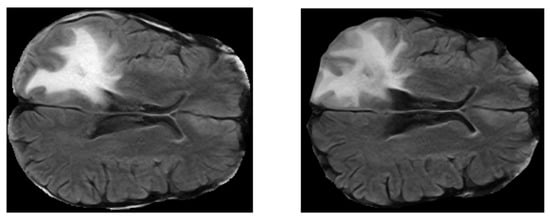

2.3. FLAIR Preprocessing

- FLAIRs were optimized by removing fat tissues and by performing skull stripping. The preprocessing steps, namely the removal of fat tissues and skull stripping, were performed by using the deep-learning algorithm described in Reference [52] (https://github.com/JanaLipkova/s3).

- From both preprocessed “pre” and “post” FLAIRs (i.e., after skull stripping) extract all the slices containing the tumor according to the corresponding ROIs.